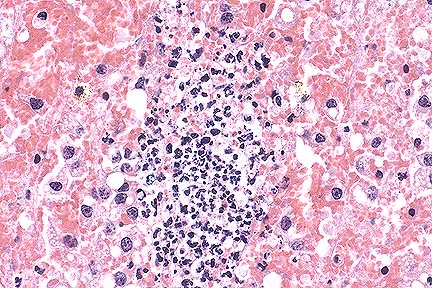

Acute ulcerative colitis in a foal treated with castor oil (HE, 200X, 50K).

Contributor's Diagnosis and Comments: Colitis, severe, focally extensive, acute, erosive and necrotizing. Castor oil-induced superficial colitis, with secondary probable endotoxin-induced submucosal thrombosis, inflammation, and mucosal necrosis.

A large area of the submucosa is thickened by edema, hemorrhage, acute inflammatory cell infiltration, lymphatic distention and venous and capillary thrombosis. The overlying mucosa in necrotic, and there are multiple surface clumps of bacteria. Adjacent viable areas of mucosa have flattened superficial epithelium, inflammatory cells between membrane and epithelium and capillary thrombosis. Severe hemorrhagic foci are present in the muscularis and serosa.

Acute superficial enterocolitis is reported in the literature following the experimental administration of castor oil to ponies. In the cecum and ventral colon, there is extensive erosion of superficial epithelium between crypts, with fibrin, neutrophils and cell debris on the denuded basement membrane. By 48 hours post ingestion, there is partial restitution of surface epithelium by flattened epithelial cells extending from the necks of crypts. Fragmented necrotic debris is sometimes present within macrophages within the lamina propria. Mucosal venules beneath the erosions are plugged with fibrin, and there is general mucosal venous congestion and distention of submucosal lymphatics.

In the equine gastrointestinal system, transit is rapid from stomach to cecum to ventral colon, but slow from ventral colon to dorsal colon, allowing prolonged exposure to toxic components. The toxic component of castor oil is ricinoleic acid. The full thickness necrosis of the mucosa and the severity of the submucosal lesion in this case suggest additional factors were operating as well as castor oil. After uncomplicated poisoning by castor oil, it is reported that repair of the mucosa is complete by 72 hours post-dosing.

AFIP Diagnosis: Colon: Colitis, necro-ulcerative, acute, focally extensive, severe, with hemorrhage, fibrin thrombi and fibrinoid vascular necrosis, Arabian, equine.